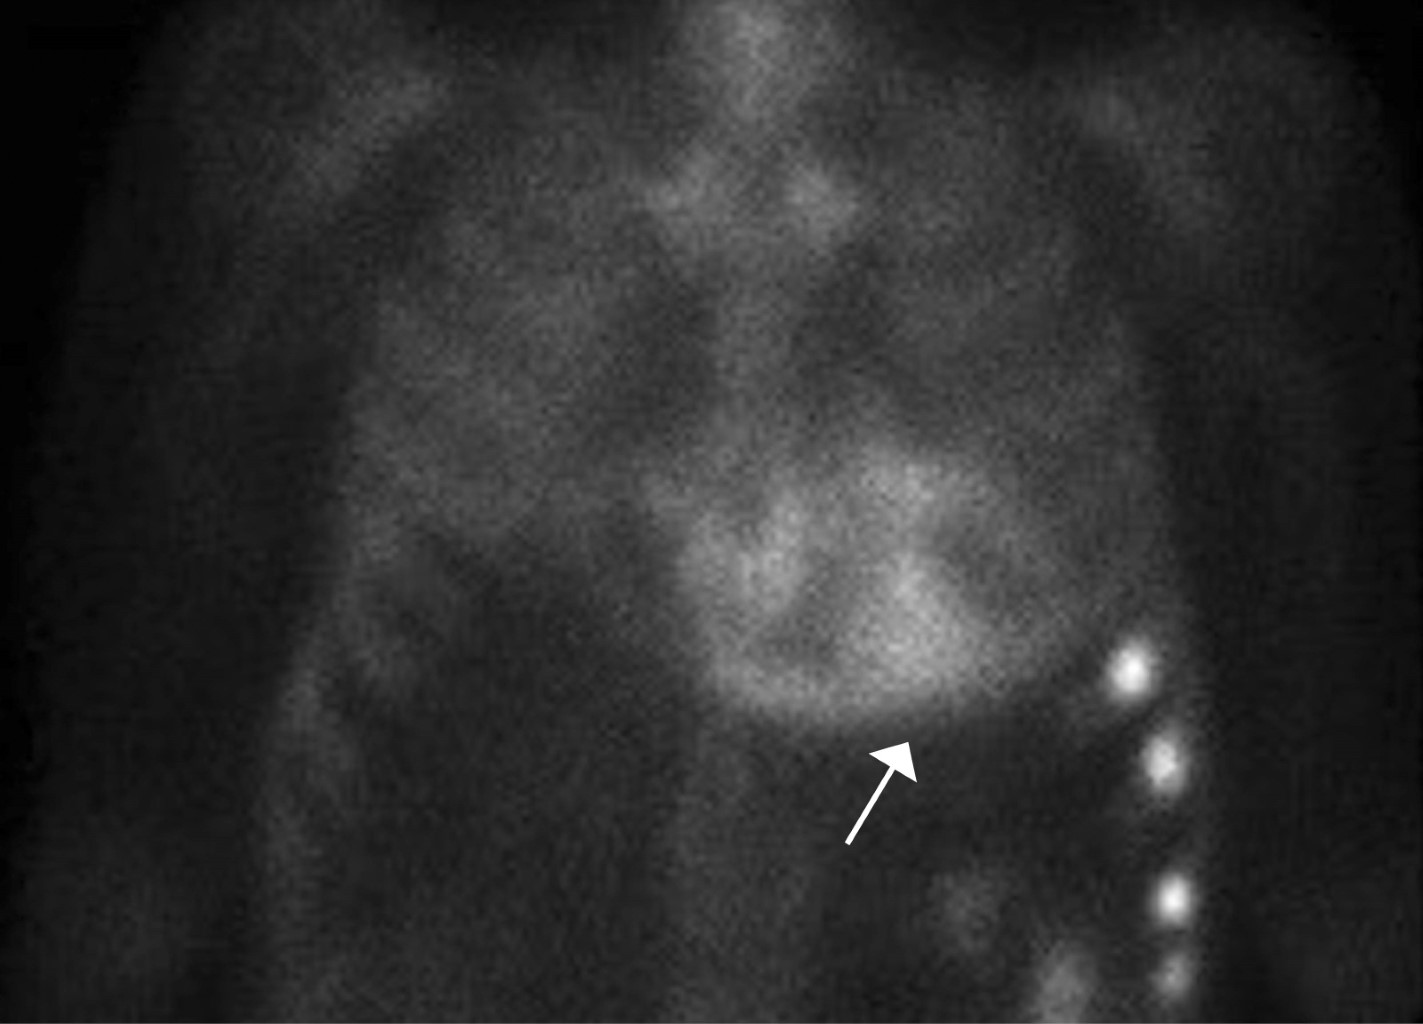

A transthoracic echocardiogram revealed a dilated left ventricle with end-diastolic diameter 60 mm, mild to moderate septal hypertrophy and severely depressed systolic function (20% LVEF by Simpson) due to global hypokinesia. He also had biatrial dilatation, a severely dilated right ventricle with depressed systolic function, mild regurgitation of the four heart valves, mild pulmonary hypertension and dilated inferior cava vein. A cardiovascular magnetic resonance (CMR) showed biventricular dilatation and systolic dysfunction (Figure 1A). High native T1 values (1304 milliseconds) and an increase in extracellular volume (40 with a 43.2% hematocryte) were reported and T1 PSIR sequences disclosed epicardic mid inferolateral, inferoseptal, subendocardial anterior and anterolateral late gadolinium enhancement (Figure 1B). These findings were compatible with infiltrative cardiomyopathy and suggestive of cardiac amyloidosis. At this point, a 99mTc-DPD bone scintigraphy, a blood and urine analysis to evaluate a possible monoclonal component -according to the latest recommendations on the diagnosis of cardiac amyloidosis4 and cardiac catheterization were requested. ATTR cardiomyopathy compatible images were reported in the scintigraphy with a significant Perugini grade 3 heart uptake of the radiotracer (Figure 2). The coronary angiography showed only mild irregularities in the left anterior descending and circumflex coronary arteries without significant obstructive lesions. The search for light chain immunoglobulin monoclonal gammopathy was negative, AL amyloid heart disease was ruled out, so ATTR cardiomyopathy was diagnosed.

Complementary tests are essential in the characterization of a congestive heart failure episode. Echocardiography is the most available tool, and it usually guides the diagnosis. In this particular case, echocardiographic images led to a DCM working diagnosis. In patients with a new onset of heart failure and DCM European guidelines suggest CMR with late gadolinium enhancement is a valuable test.5 It can provide information about potential ischaemic or non-ischaemic etiology and guide the differential diagnosis of non-ischaemic causes. In this case report, the CMR gave important clues toward the correct diagnosis of infiltrative amyloid cardiac disease (hypertrophy, compatible enhancement, high extracellular volume and native T1 values). Besides, the absence of monoclonal light chain immunoglobulin and the evident Perugini grade 3 radiotracer uptake in the scintigraphy provided the ATTR cardiomyopathy definitive diagnosis without endomyocardial biopsy.4

Figure 2